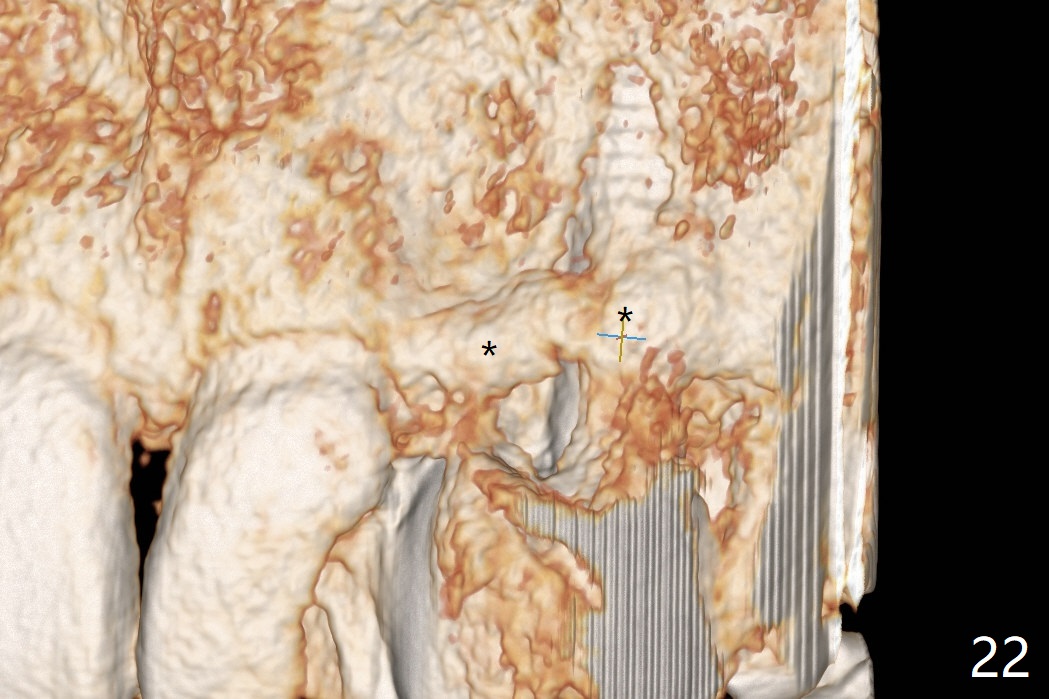

18岁男从外州大学回来,无症状,但是6号牙(右上尖牙)颊侧瘘道(图一,二(角化龈充分(箭头))),根尖片显示植体近中骨吸收(图三:*),而对侧植体仿佛骨整合(图四)。患侧切开后发现植体颊侧暴露,松动。拔除后骨缺损由粘性骨粉修复(图七,九:*),覆盖PRF膜(图七:P)和带钛网(图九:^)不可吸收膜(图五-七),后者用两个小钉子固定(图六(腭侧),七(颊侧),九),使用新的刀片和一个特殊尖头剥离器在颊侧骨膜下相当广泛分离,使用PTFE缝线,粘膜下水平褥式缝合之后(图八:箭头),多个垂直间断缝合,两个乳头垂直褥式缝合。术后一周伤口没有裂开,术后疼痛肿胀已经消退(图十)。术后十八天牙槽嵴仿佛比对侧还要宽(图十一,三与图十二,四(取模)对比)。术后5.5个月伤口没有裂开,牙槽骨,角化龈宽(图十六),与钛网和两个小钉子固定有关(图十五,十七)。CT显示牙槽骨只能容纳2.5或者3.0毫米植体(图十八)。11号牙植体牙冠粘固后没有骨质吸收(图十九),其实10,11号牙颊侧骨板隆起(图二十至二十二),而6植体失败,颊侧骨板吸收,甚至累及5号牙(图十七)。